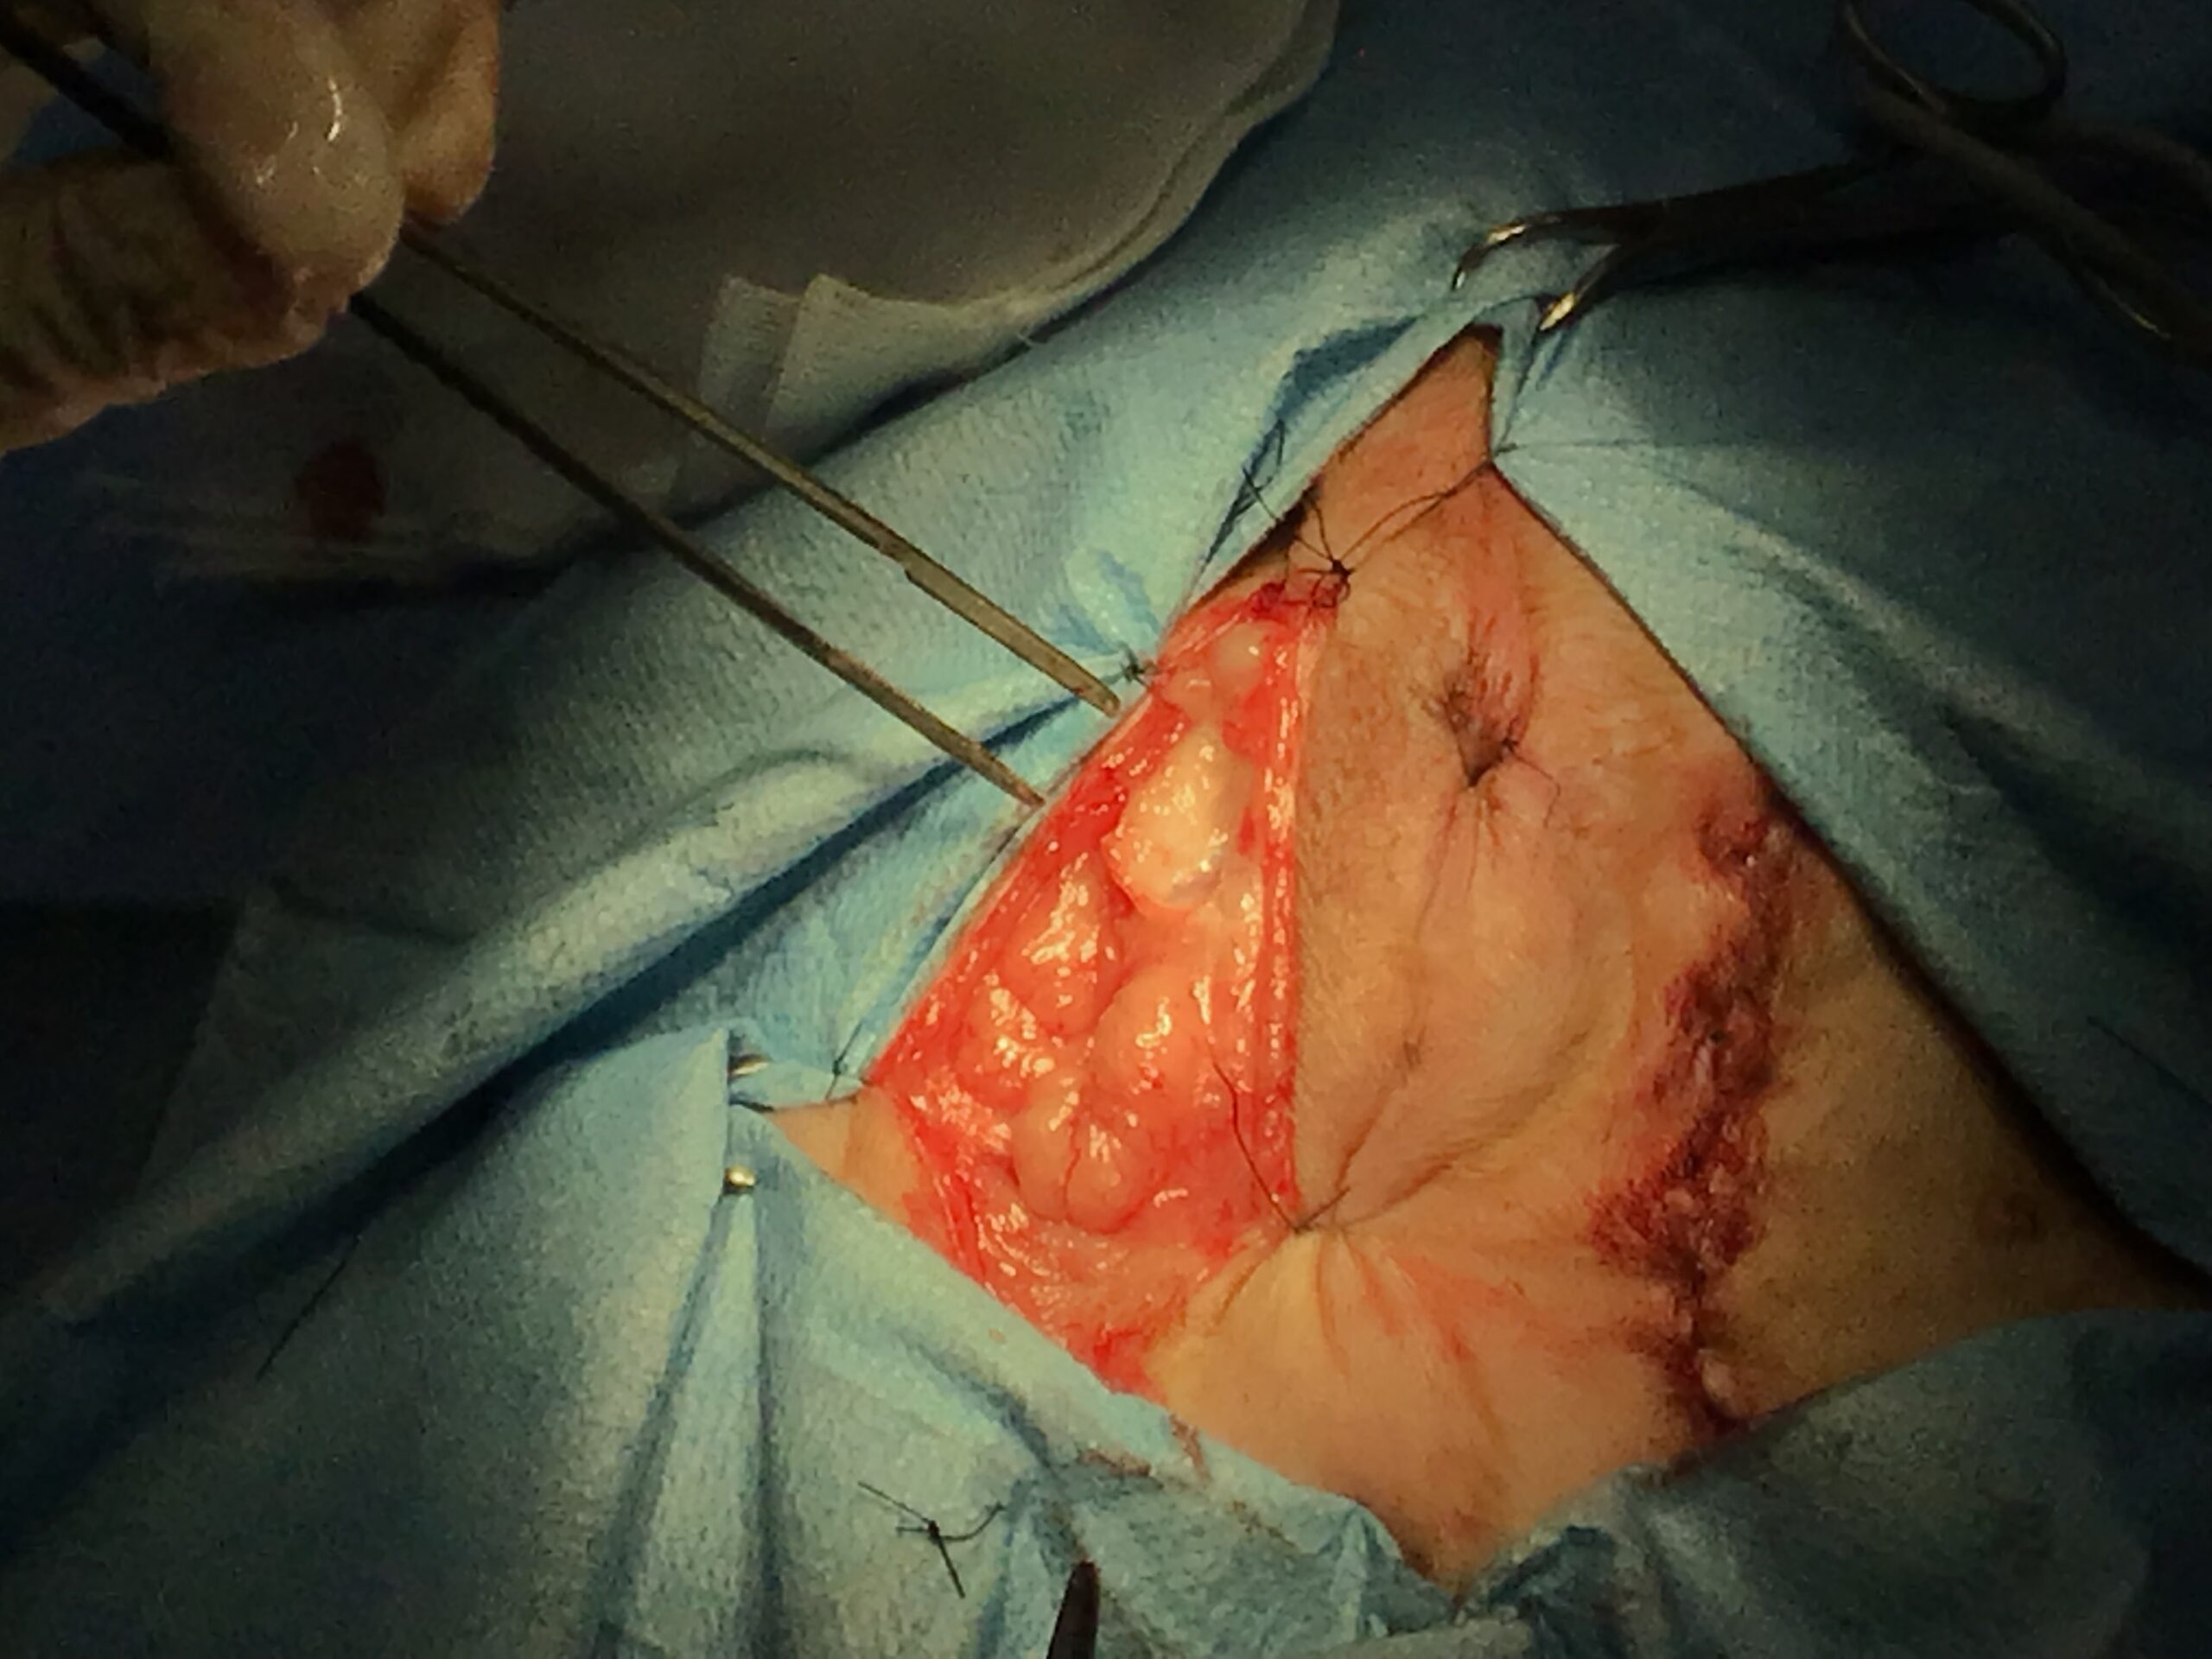

本症例は、心疾患(僧帽弁逸脱)および頸部気管虚脱という、全身麻酔において極めてリスクの高い基礎疾患を抱えていました。これらの疾患がある場合、術中の急激な血圧低下や術後の呼吸停止リスクが跳ね上がります。

このハイリスクな状況下で安全域を極限まで広げるため、当院では「局所浸潤麻酔」を徹底して活用しています。心血管系への抑制が強い硬膜外麻酔は当院では一切使用しません。局所浸潤麻酔による確実な末梢の疼痛ブロックと、緻密な術中血圧・呼吸管理を組み合わせることで、心肺機能への負担を最小限に抑えています。

本症例には、時期を分けて2つの大きな外科的介入を行いました。

This post details our surgical and medical approach to a complex case involving recurrent severe perineal hernia and a malignant liver lymphoma in a senior dog. We emphasize the grim reality of untreated conditions and the severe risks of anesthesia when underlying heart and respiratory diseases are present. To maximize safety, we exclusively use local infiltration anesthesia. Due to a lack of available autologous tissue, a polypropylene mesh and extensive organ pexy (both colon and bladder fixation to the abdominal wall) were required to prevent fatal urethral obstruction and re-herniation. Additionally, simultaneous castration was performed to shrink the enlarged prostate, a key factor in hernia development, thereby reducing the risk of recurrence. For the liver tumor, given its deep location at the liver base and the high risk of fatal bleeding, we opted for a biopsy which confirmed lymphoma. Unfortunately, the patient’s elevated bilirubin and the family’s preference for a compromised, single-agent chemotherapy protocol led to early drug resistance. We candidly discuss the harsh realities of end-stage cancer—it is a painful decline characterized by severe cachexia and organ failure that palliative care can only partially ease. Furthermore, we outline our strict early discharge policy (1-3 days), the physical limitations of our unstaffed overnight remote monitoring, and our referral policy for highly specialized surgeries. We believe in providing honest, logical medical facts rather than false hope, ensuring families can make fully informed and responsible decisions.